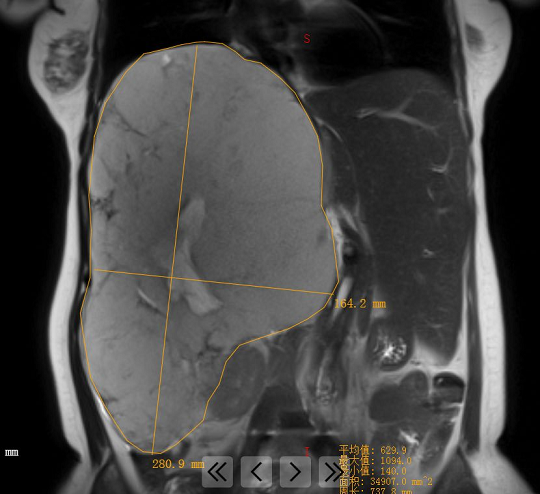

圖為患者肝巨大血管瘤的影像資料。